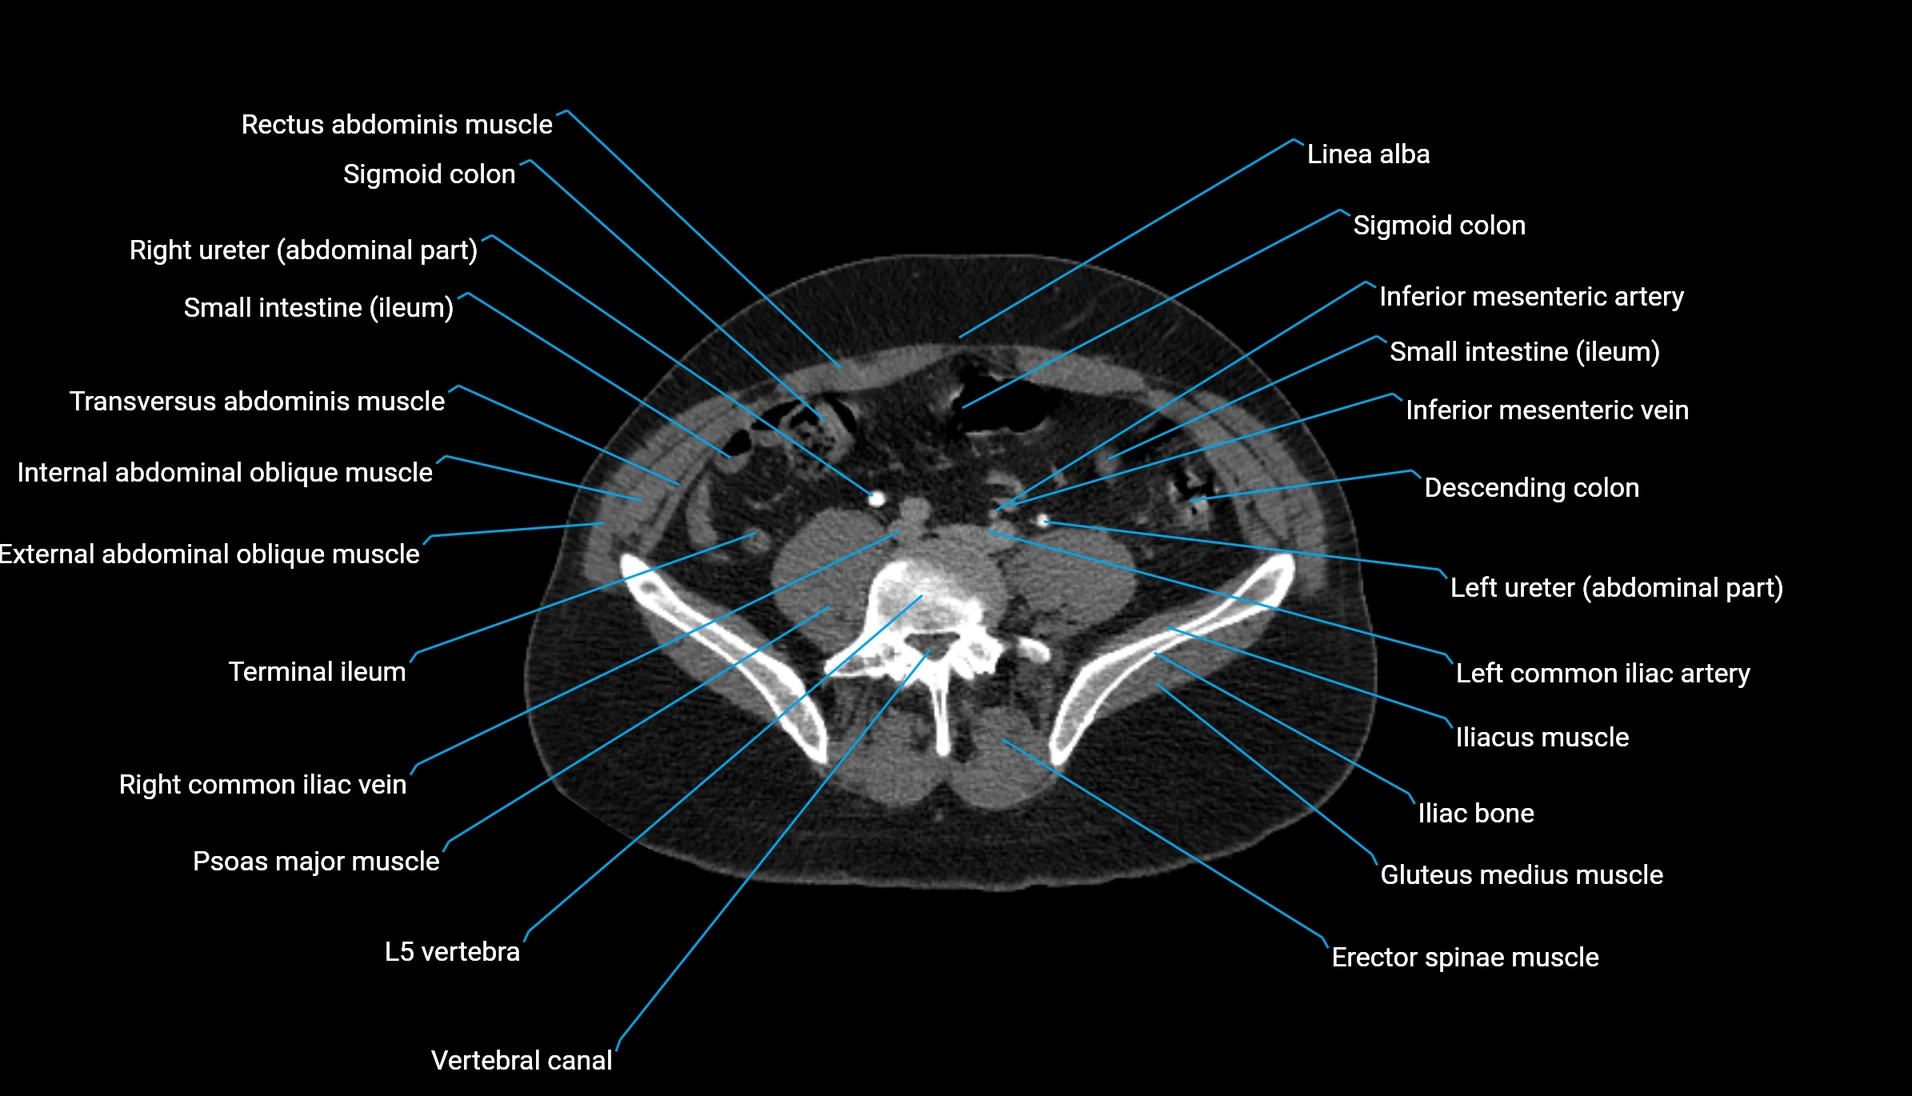

CT VRT 3D image

CT image